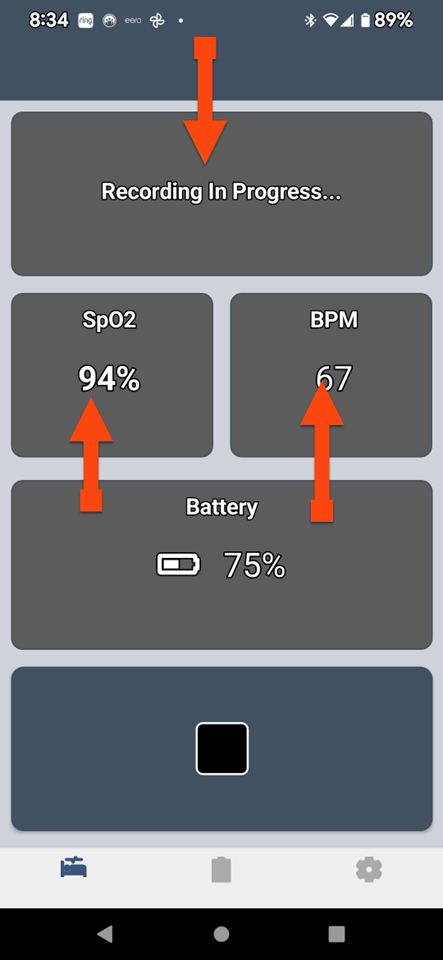

SLEEPIMAGE APP (Android)

SLEEPIMAGE APP (Android)

SLEEPIMAGE APP (Android)

SLEEPIMAGE APP (Android)

SLEEPIMAGE APP (Android)

SLEEPIMAGE APP (Android)

SLEEPIMAGE APP (Android)

SLEEPIMAGE APP (Android)

SLEEPIMAGE APP (Android)

SLEEPIMAGE APP (Android)

SLEEPIMAGE APP (Android)

SLEEPIMAGE APP (Android)

SLEEPIMAGE APP (Android)

SLEEPIMAGE APP (Android)

SLEEPIMAGE APP (Android)

SLEEPIMAGE APP (Android)

SLEEPIMAGE APP (Android)

SLEEPIMAGE APP (Android)

SLEEPIMAGE APP (Android)

SLEEPIMAGE APP (Android)

SLEEPIMAGE APP (Android)

SLEEPIMAGE APP (Android)

SLEEPIMAGE APP (Android)

SLEEPIMAGE APP (Android)

SLEEPIMAGE APP (Android)

SLEEPIMAGE APP (Android)

SLEEPIMAGE APP (Android)

SLEEPIMAGE APP (Android)

SLEEPIMAGE APP (Android)